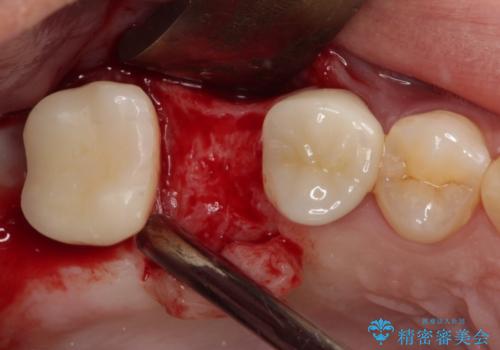

最後方歯は、クラウンを維持するための高さが不足していたため、インプラント処置の際に歯冠長を延長する手術を併用し、維持力を増すこととしました。

上顎洞までの骨高さが低いケースでしたが、ショートインプラントと骨圧縮機能を持つドリルの使用により、上顎洞底挙上を行うことなく、インプラント治療を行うことができました。